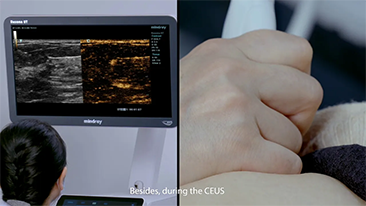

Mindray Resona-oplossingen voor algemene beeldvorming helpen clinici bij het realiseren van nauwkeurigere en effici?ntere diagnose- en behandelingsresultaten door middel van sondes voor aparte toepassingen en effici?nte klinische toepassingstools.

Inzichten

De medische omgeving van vandaag is complexer geworden, met een toenemend aantal moeilijke gevallen en meer werkdruk.